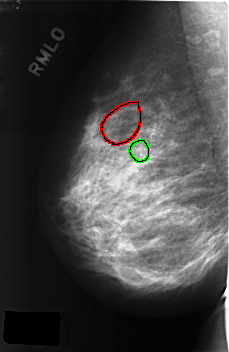

C_0309_1.RIGHT_MLO

FILE: C_0309_1.RIGHT_MLO.OVERLAY

TOTAL_ABNORMALITIES 2

ABNORMALITY 1

LESION_TYPE CALCIFICATION TYPE PLEOMORPHIC DISTRIBUTION CLUSTERED

ASSESSMENT 5

SUBTLETY 3

PATHOLOGY MALIGNANT

TOTAL_OUTLINES 1

BOUNDARY

ABNORMALITY 2

LESION_TYPE CALCIFICATION TYPE AMORPHOUS DISTRIBUTION CLUSTERED

ASSESSMENT 4

PATHOLOGY BENIGN